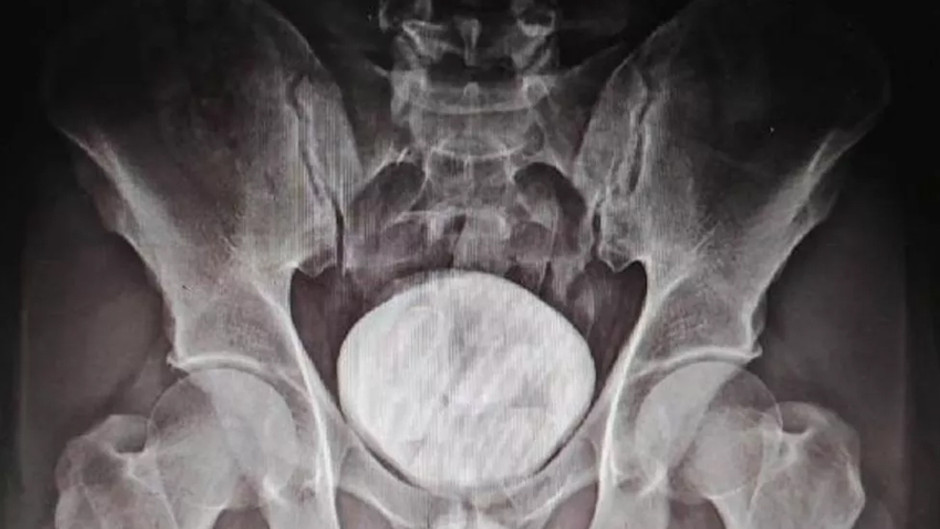

RÖNTGENDE TESPİT EDİLDİ

Kars Harakani Devlet Hastanesi’ne götürülen Tazehkand’ın çekilen röntgeninde, makatında uyuşturucu tespit edildi. Uyuşturucuyu doğal yollardan çıkaran Tazehkand, gözaltına alındı. Emniyetteki işlemlerinin ardından adliyeye sevk edilen şüpheli, çıkarıldığı hakimlikçe tutuklandı.